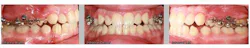

Case report

A healthy 15-year-old male presents to the clinic with an anterior open bite. His case is outlined in the figures below.

The patient in the above case report is still in active treatment. Now that successful maxillary posterior intrusion has been accomplished, the remaining full, fixed orthodontic appliances can be placed. The TPA can be removed and the molar intrusion will be held for the remainder of treatment with a ligature tie placed from the first molar to the TADs. The TADs will be kept in place for the remainder of treatment to maintain the stability of the intrusion as bone remodeling occurs.